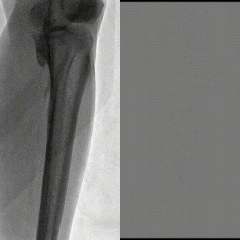

右股总-髂外闭塞,左股-腘动脉全程闭塞,膝下流出道显示不清,重度钙化

图:术前CT

图:造影显示,股腘动脉全程闭塞,膝下流出道差